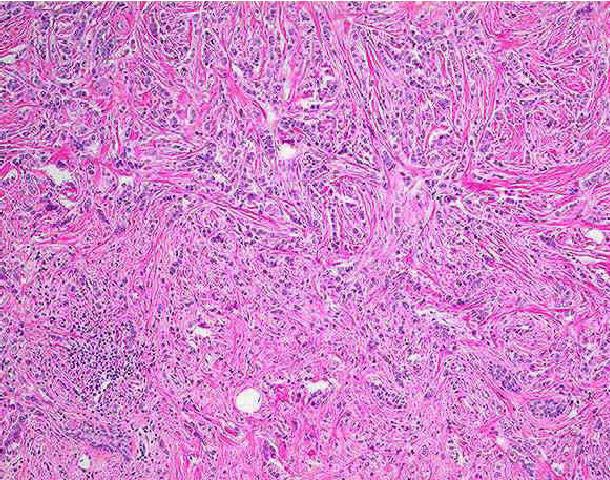

Một số hình ảnh giải phẫu bệnh lý của u biểu mô tuyến vú:

H6: Ung thư biểu mô thùy xâm nhập thể điển hình